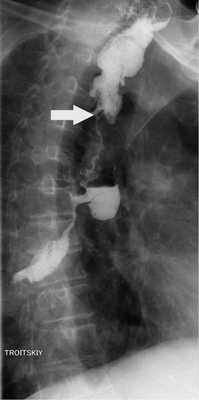

Обследование в МКНЦ

По данным эзофагоскопии, от верхней трети пищевода его слизистая отечна, белесая, с множественными рубцами. На расстоянии 35 см от резцов выявлена циркулярная язва, покрытая фибрином, и стриктура, суживающая просвет пищевода до 0,4 см. Осмотреть дистальные отделы пищевода и желудок стандартным эндоскопом на данном этапе не удалось. Рентгенография: протяженность рубцовой стриктуры до 12 см. Она захватывает нижнюю и среднюю треть пищевода. Супрастенотически пищевод расширен до 4 см (рис. 1). Патологических изменений в желудке не выявлено.

Рис. 1. Рентгенограмма. Протяженность стриктуры (стрелки).